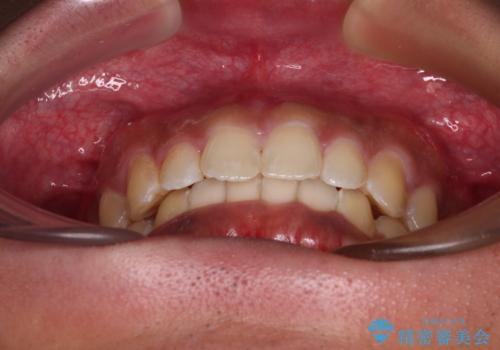

デコボコとディープバイトを治したい インビザラインによる矯正治療

- 前歯のデコボコや隙間と深い咬み合わせ(ディープバイト)を気にして来院された患者様です。

インビザラインによる上下歯列の側方拡大と後方移動、IPR(歯と歯の間を削る)にるスペースの獲得により、デコボコとディープバイトを改善することとしました。

気になっていたデコボコや隙間は改善し、きれいな歯列に整えることができました。

咬合力が非常に強い方であったため、これ以上のディープバイトの改善は困難となりました。